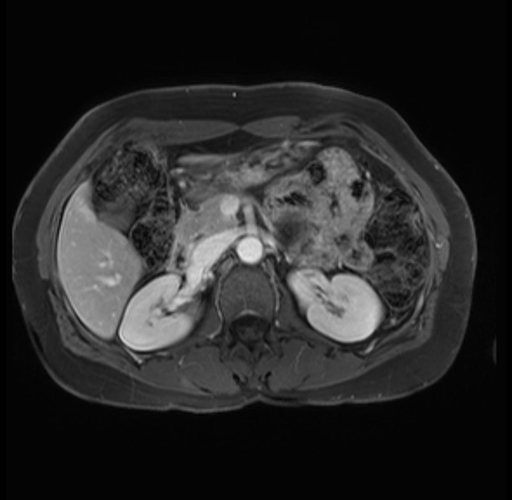

Imaging Analysis

Look through the patient's CT scan to identify any areas of concern for the necessary procedure.

Based on your CT findings, which issue(s) are present and would give reason for "planned slowing down moment(s)" in this case?

Considering a standard distal pancreatectomy procedure, what step(s) of the operation would you do differently in this case?